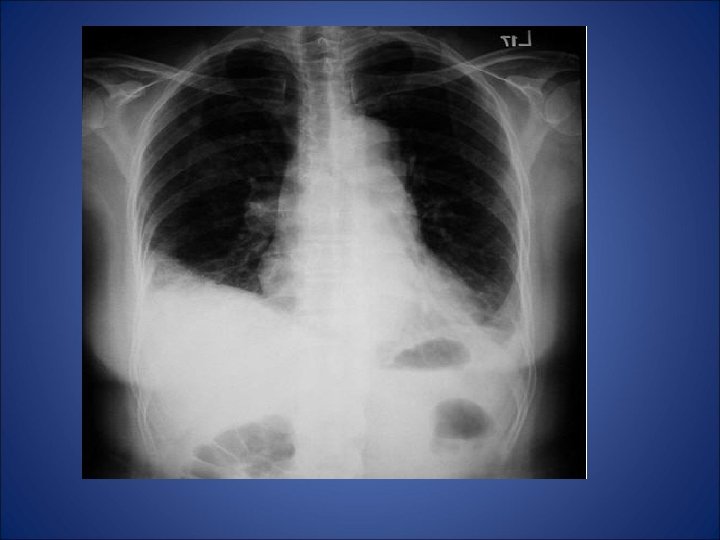

RX toracic

• Care este diagnosticul pacientului?

Embolism pulmonar acut • - desi simptomele clinice indica embolismul pulmonar (durere pleuritica, dispnee), pacientul din cazul de fata nu prezinta niciun factor de risc (chiar mai mult ca factori de preventie avem varsta si activitatea fizica) - pentru certitudine s-a folosit investigatia CT care a relevat multipli emboli atat in vascularizatia majora a plamanului stang cat si a celui drept - orice evaluarea ulterioara a pacientului nu a putut elucida cauza embolismului. • Nu exista suficiente referiri la naproxen in cazurile raportate de embolism pulmonar si astfel nu poate fi incriminat pentru producerea acestui fenomen. Mai mult, dupa tratamentul intraspitalicesc pacientul a refuzat tratamentul cu warfarina si la la cateva luni au aparut alte episoade de embolism. Decizia terapeutica finala a fost plasarea unui filtru Greenfield de vena cava inferioara.